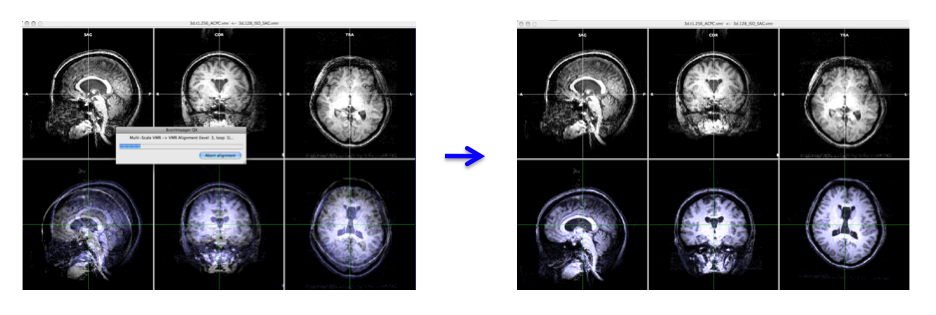

Since the epi image has low resolution, we align the low resolution anatomical image instead of the epi image to high resolution anatomical image and make a transformation file. We will use this file for epi image - high resolution anatomical image coregistration.

- Open anat.high.vmr file

- In the "3D Volume Tools" dialogue, choose "Coregistration" and click "Select VMR..." button to select anat.low_SAG_ISO.vmr file for VMR-VMR coregistration.

Press "Align..." then "GO" in the "VMR-VMR Coregistration Options" dialogue. - Select "Spatial Transf" and click "Save .TRF" to save the parameter file for this spatial transformation.

-> You will get the anat.high_Man.trf file.